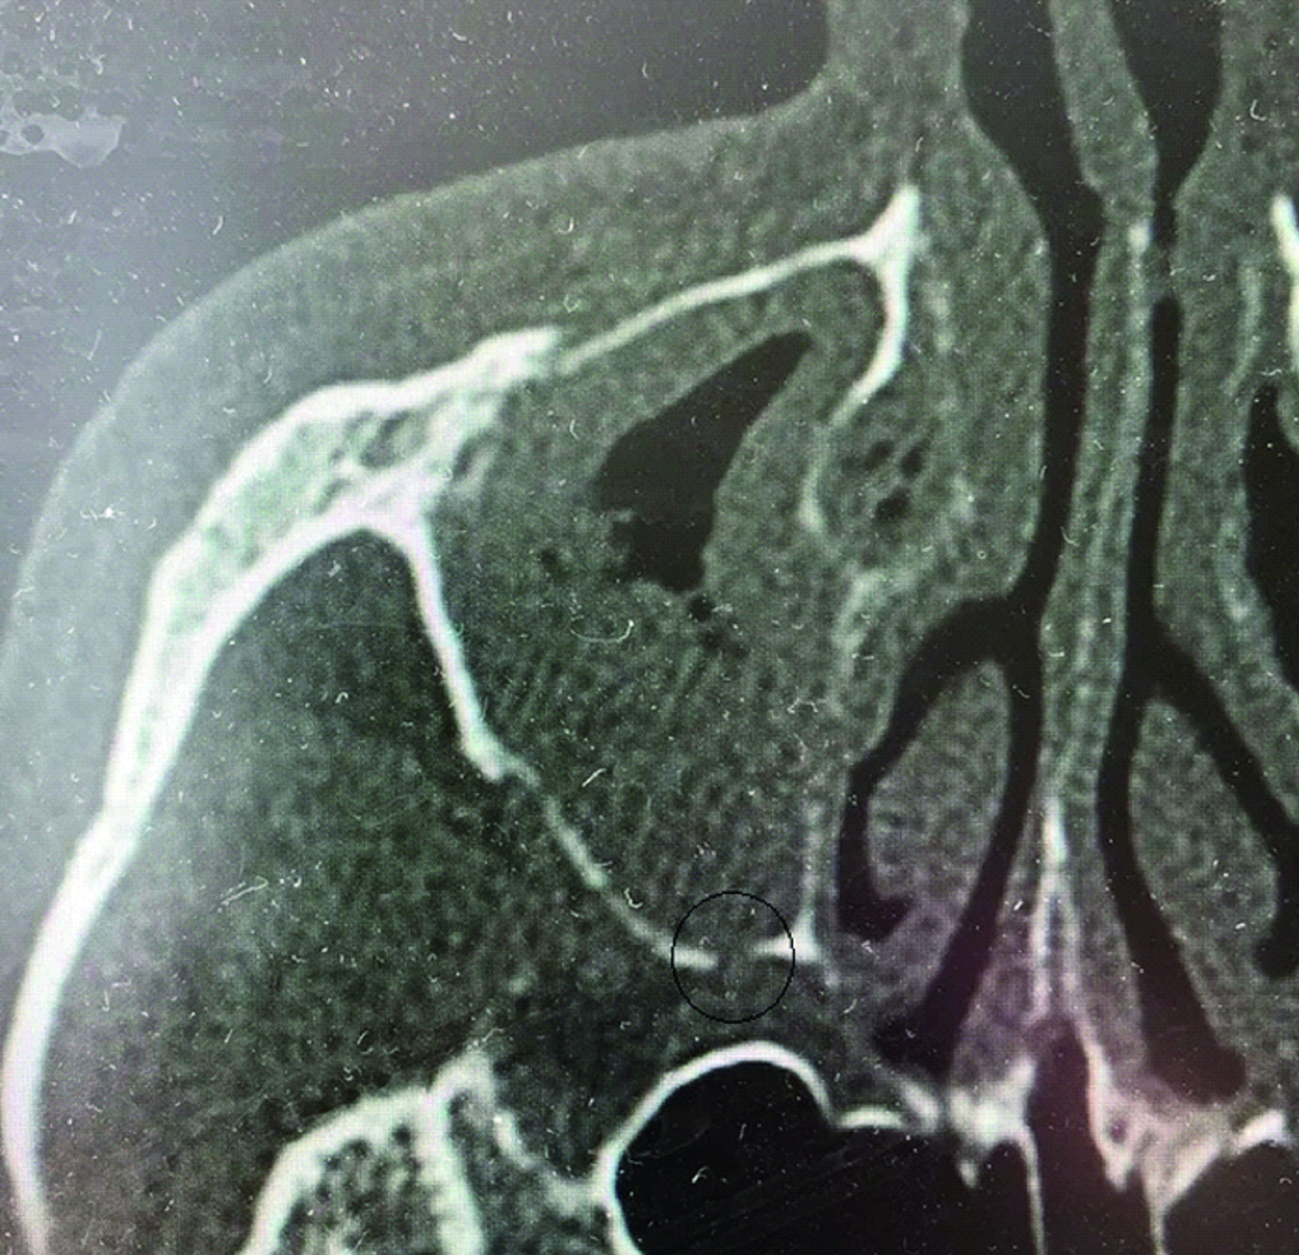

На вторые сутки пребывания в лор-отделении многопрофильной больницы удалена передняя и задняя тампонада полости носа. Данных за продолжающееся кровотечение нет. Выполнено КТ ОНП с контрастом после эмболизации и удаления тампонады – визуализирован дефект задней стенки верхнечелюстной пазухи справа, содержимое в правой верхнечелюстной пазухе, вероятнее всего геморрагические сгустки (рисунок 1). Пациент выписан под наблюдение врача оториноларинголога поликлиники по месту жительства в удовлетворительном состоянии.

Рисунок 1. КТ околоносовых пазух через 2 дня после удаления тампонады и эмболизации верхнечелюстной артерии. Визуализируется дефект задней стенки верхнечелюстной пазухи.

Figure 1. CT imaging of the paranasal sinuses 2 days after tamponade removal and embolization of the maxillary artery. A defect in the posterior wall of the maxillary sinus is visualized.